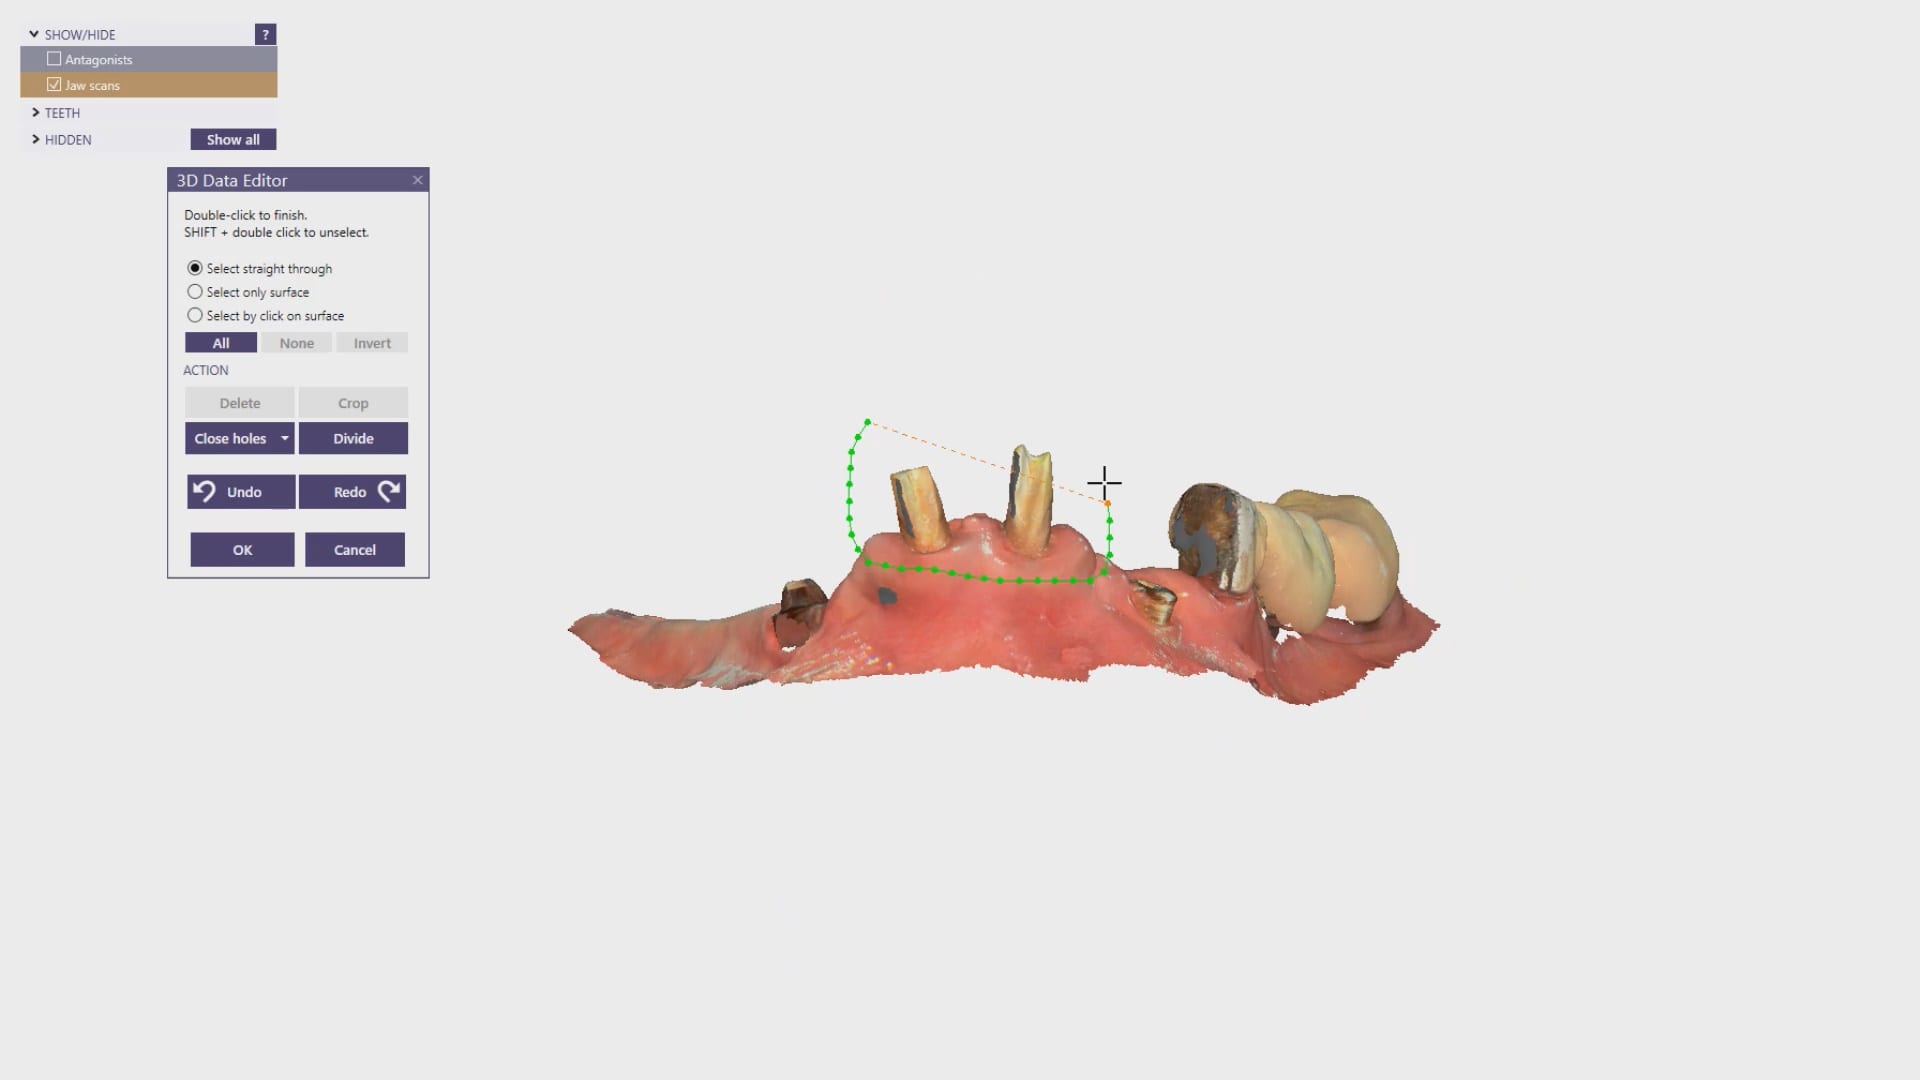

Digital extractions performed in preparation for overdentures

Overdenture Design and Fabrication